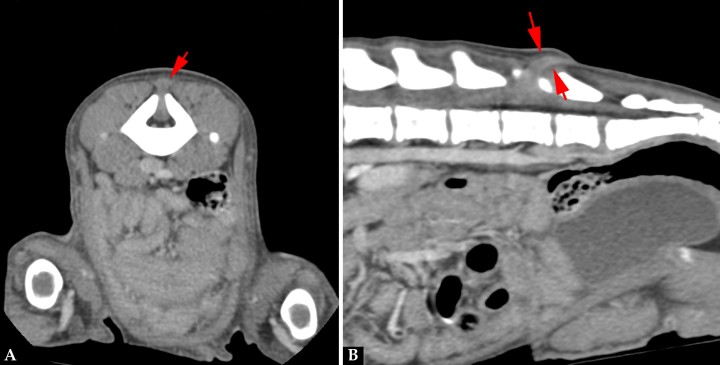

La mielografía podría ayudarnos a valorar el espacio subaracnoideo si sospechamos de un MC/MMC, aunque las técnicas de imagen avanzada, tomografía computarizada (TC) y resonancia magnética (RM) son las pruebas recomendadas si se sospecha de un defecto del tubo neural (DTN). Se realizó un estudio TC (General Electric Brivo CT385 Series de 16 cortes, Hangwei Medical Systems Co Ltd, Beijing, China, 16 cortes) sin y con contraste intravenoso, en el que se observó hipoplasia de la apófisis espinosa de L6 sin fusión de las láminas dorsales dejando un espacio abierto que comunicaba el canal vertebral y el tejido blando lumbar caudodorsal a L6 (Fig. 3). En las imágenes obtenidas en ventana de tejidos blandos tras administración de contraste se apreció el paso por el defecto espinal de tejido del canal vertebral con atenuación tejido blando y realce periférico, hasta el tejido blando dorsal a L6-7 (Fig. 4).

Figura 4

Imágenes de TC en ventana de tejidos blandos postcontraste. (A) Plano transversal. Defecto óseo vertebral con paso de tejido del canal vertebral, con atenuación tejido blando y realce periférico, hasta el tejido blando dorsal a L6-7 (flecha roja). (B) Reconstrucción en plano sagital.

Los hallazgos tomográficos indicaban la presencia de un DTN, espina bífida y MC/MMC. El diagnóstico diferencial incluiría un seno dermoide (SD) y el síndrome de médula anclada.